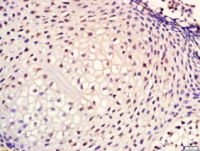

WB=1:500-2000 ELISA=1:500-1000 IHC-P=1:400-800 IHC-F=1:400-800 IF=1:100-500

Phospho-CDK2 (Thr160)

磷酸化周期素依赖性激酶2抗体